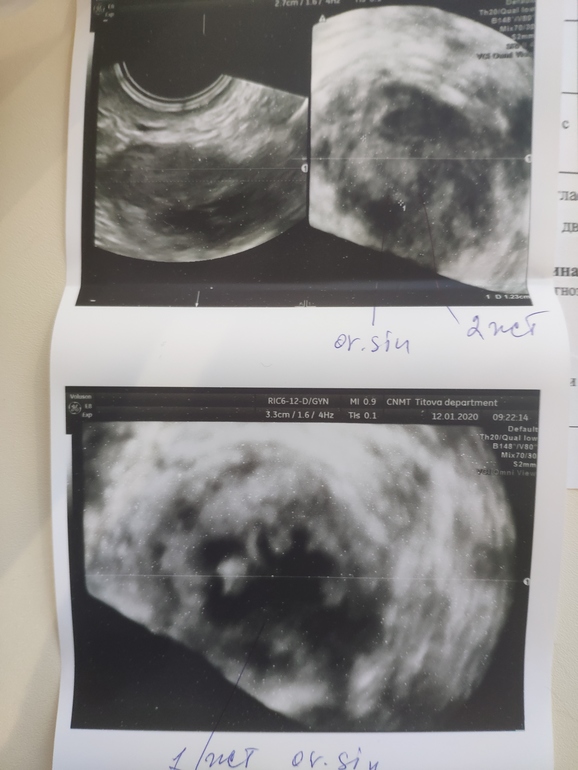

2 жёлтых тела, у кого было?

ФолликулометрияДевочки, может второе, это с прошлого цикла? Но почему у него тогда кровоток есть🤷 Доминантный фоликул вроде один был.

Конечно бывает, но не у всех и не часто. У меня не в одном два овулировали, а в обоих по яичниках по желтому телу каждый цикл.

Значит совулировали два фолликула. Бывает что на узи увидели большой один, а к моменту овуляции подоспел и второй